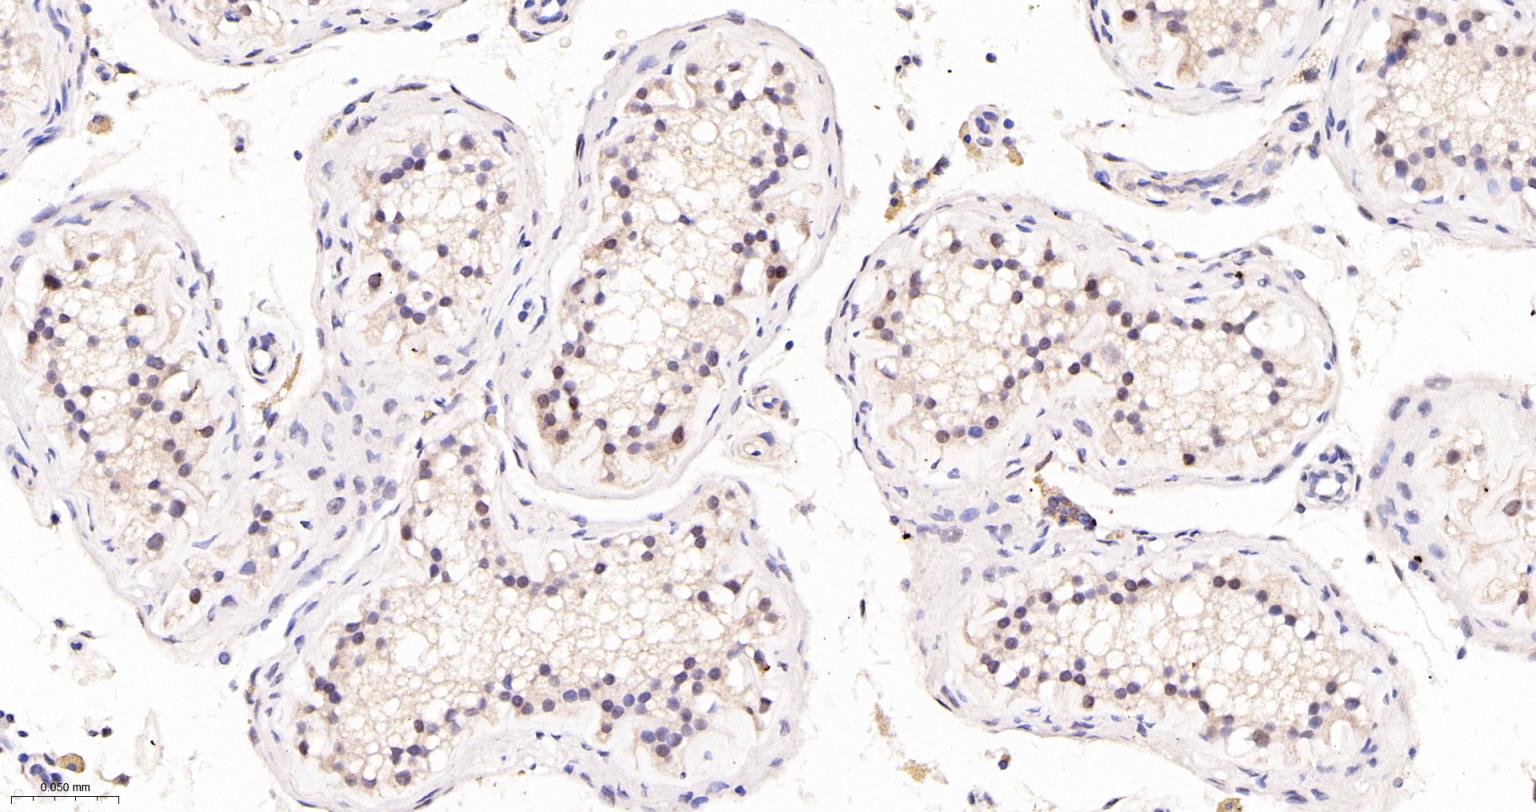

Paraformaldehyde-fixed, paraffin embedded Human Testicles; Antigen retrieval by boiling in sodium citrate buffer (pH6.0) for 15 min; The section was incubated with TEAD1 Monoclonal Antibody, Unconjugated (bsm-63274R) at 1:200 overnight at 4°C, followed by conjugation to the bs-0295G-HRP and DAB (C-0010) staining.